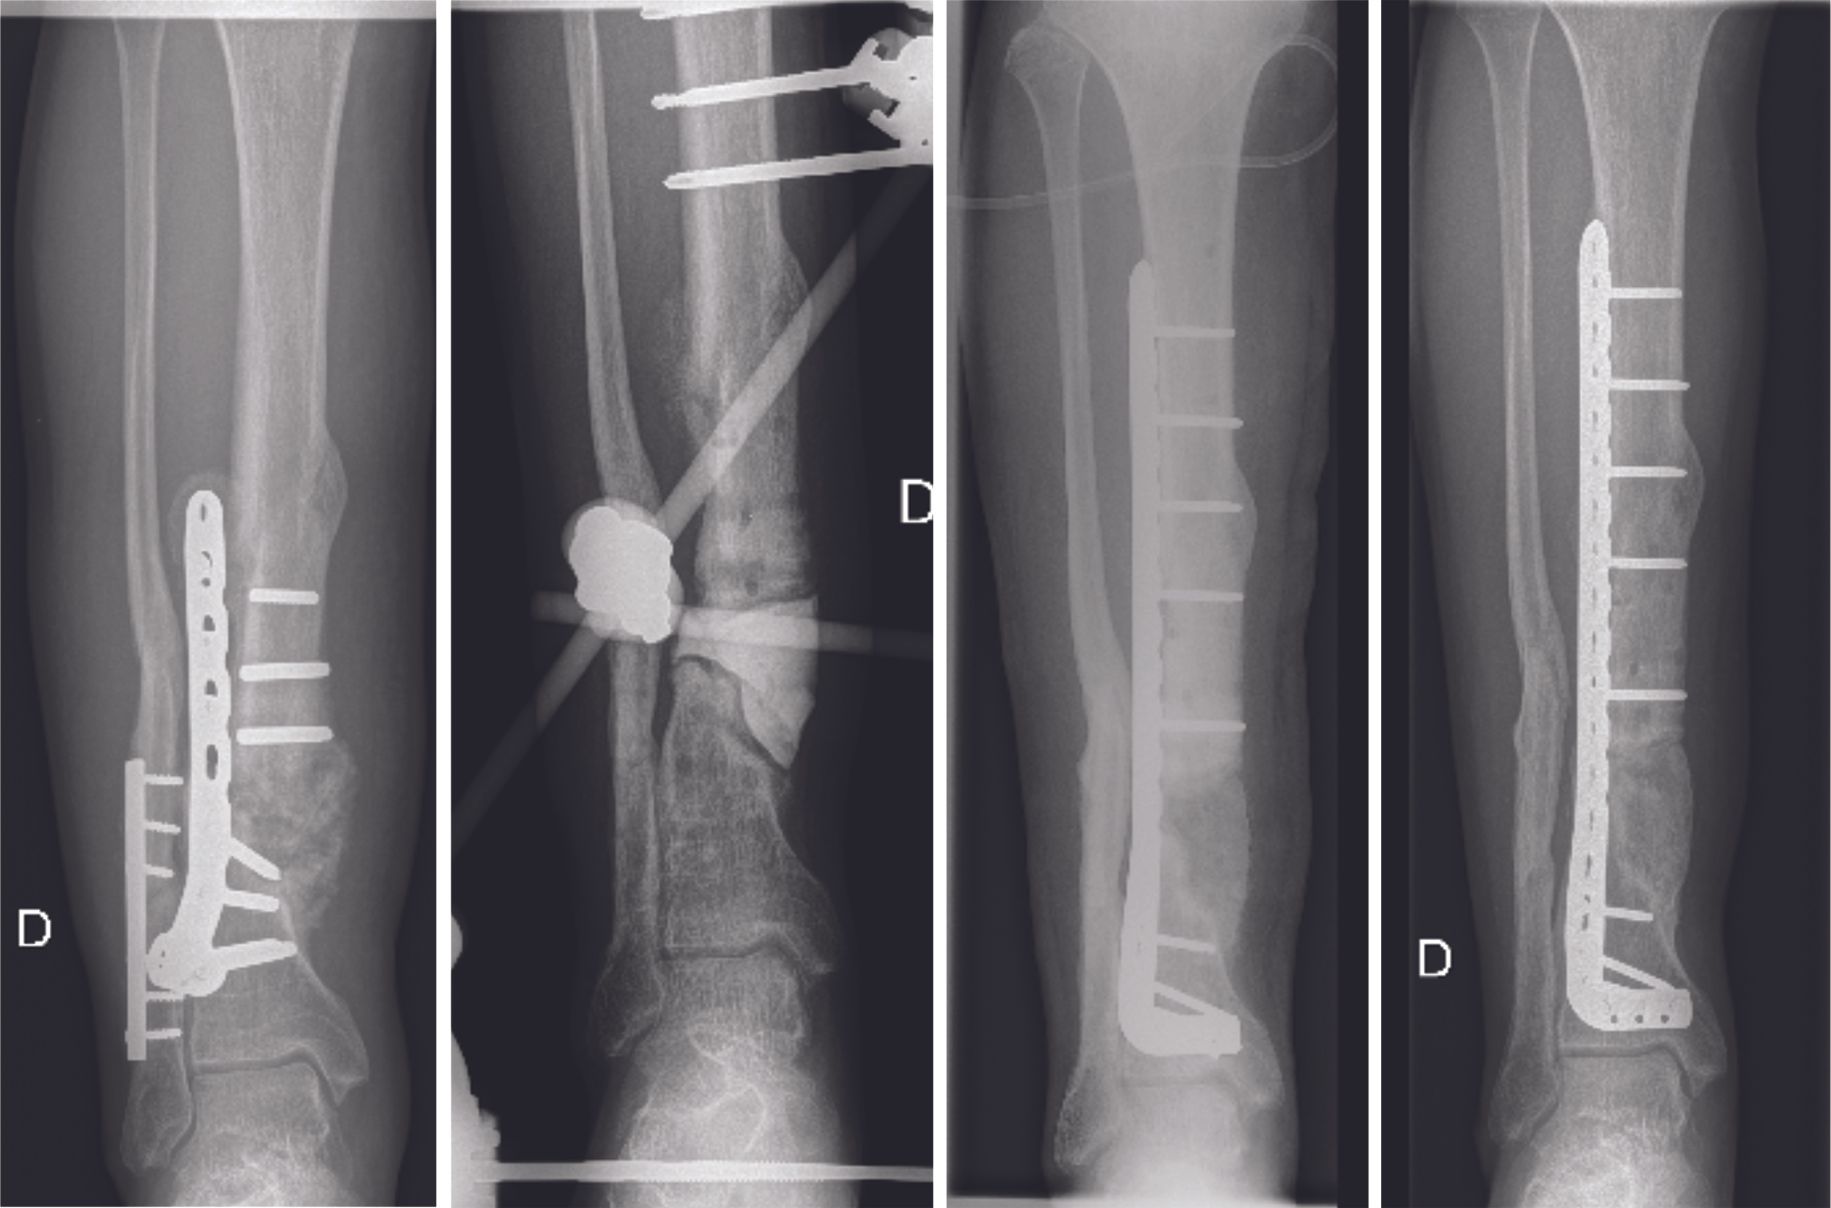

The second surgical stage includes removal of the cement spacer, bony reconstruction by bone grafting and final osteosynthesis (Fig. 4 and 5). The spacer is replaced by bone grafts harvested using the RIA (reamer – irrigator – aspirator) technique. The RIA technique allows large amounts of quality bone graft to be harvested if necessary. The induced membrane of the Masquelet technique avoids resorption of the bone graft and allows secondary bone healing.

The therapeutic strategy is to perform a resection of the pseudarthrosis until healthy bone is encountered (Fig. 6 A), insert an antibiotic bone cement spacer (Fig. 6 B) and then combine these local antibiotics with intravenous antibiotic therapy. In a second stage, which should be performed at least 6 weeks later, the surgeon replaces the spacer with a bone graft using the Masquelet technique or an intercalary prosthesis (Fig. 6 C). Intravenous antibiotic therapy should continue for several weeks post-surgery, depending on the type of infection.